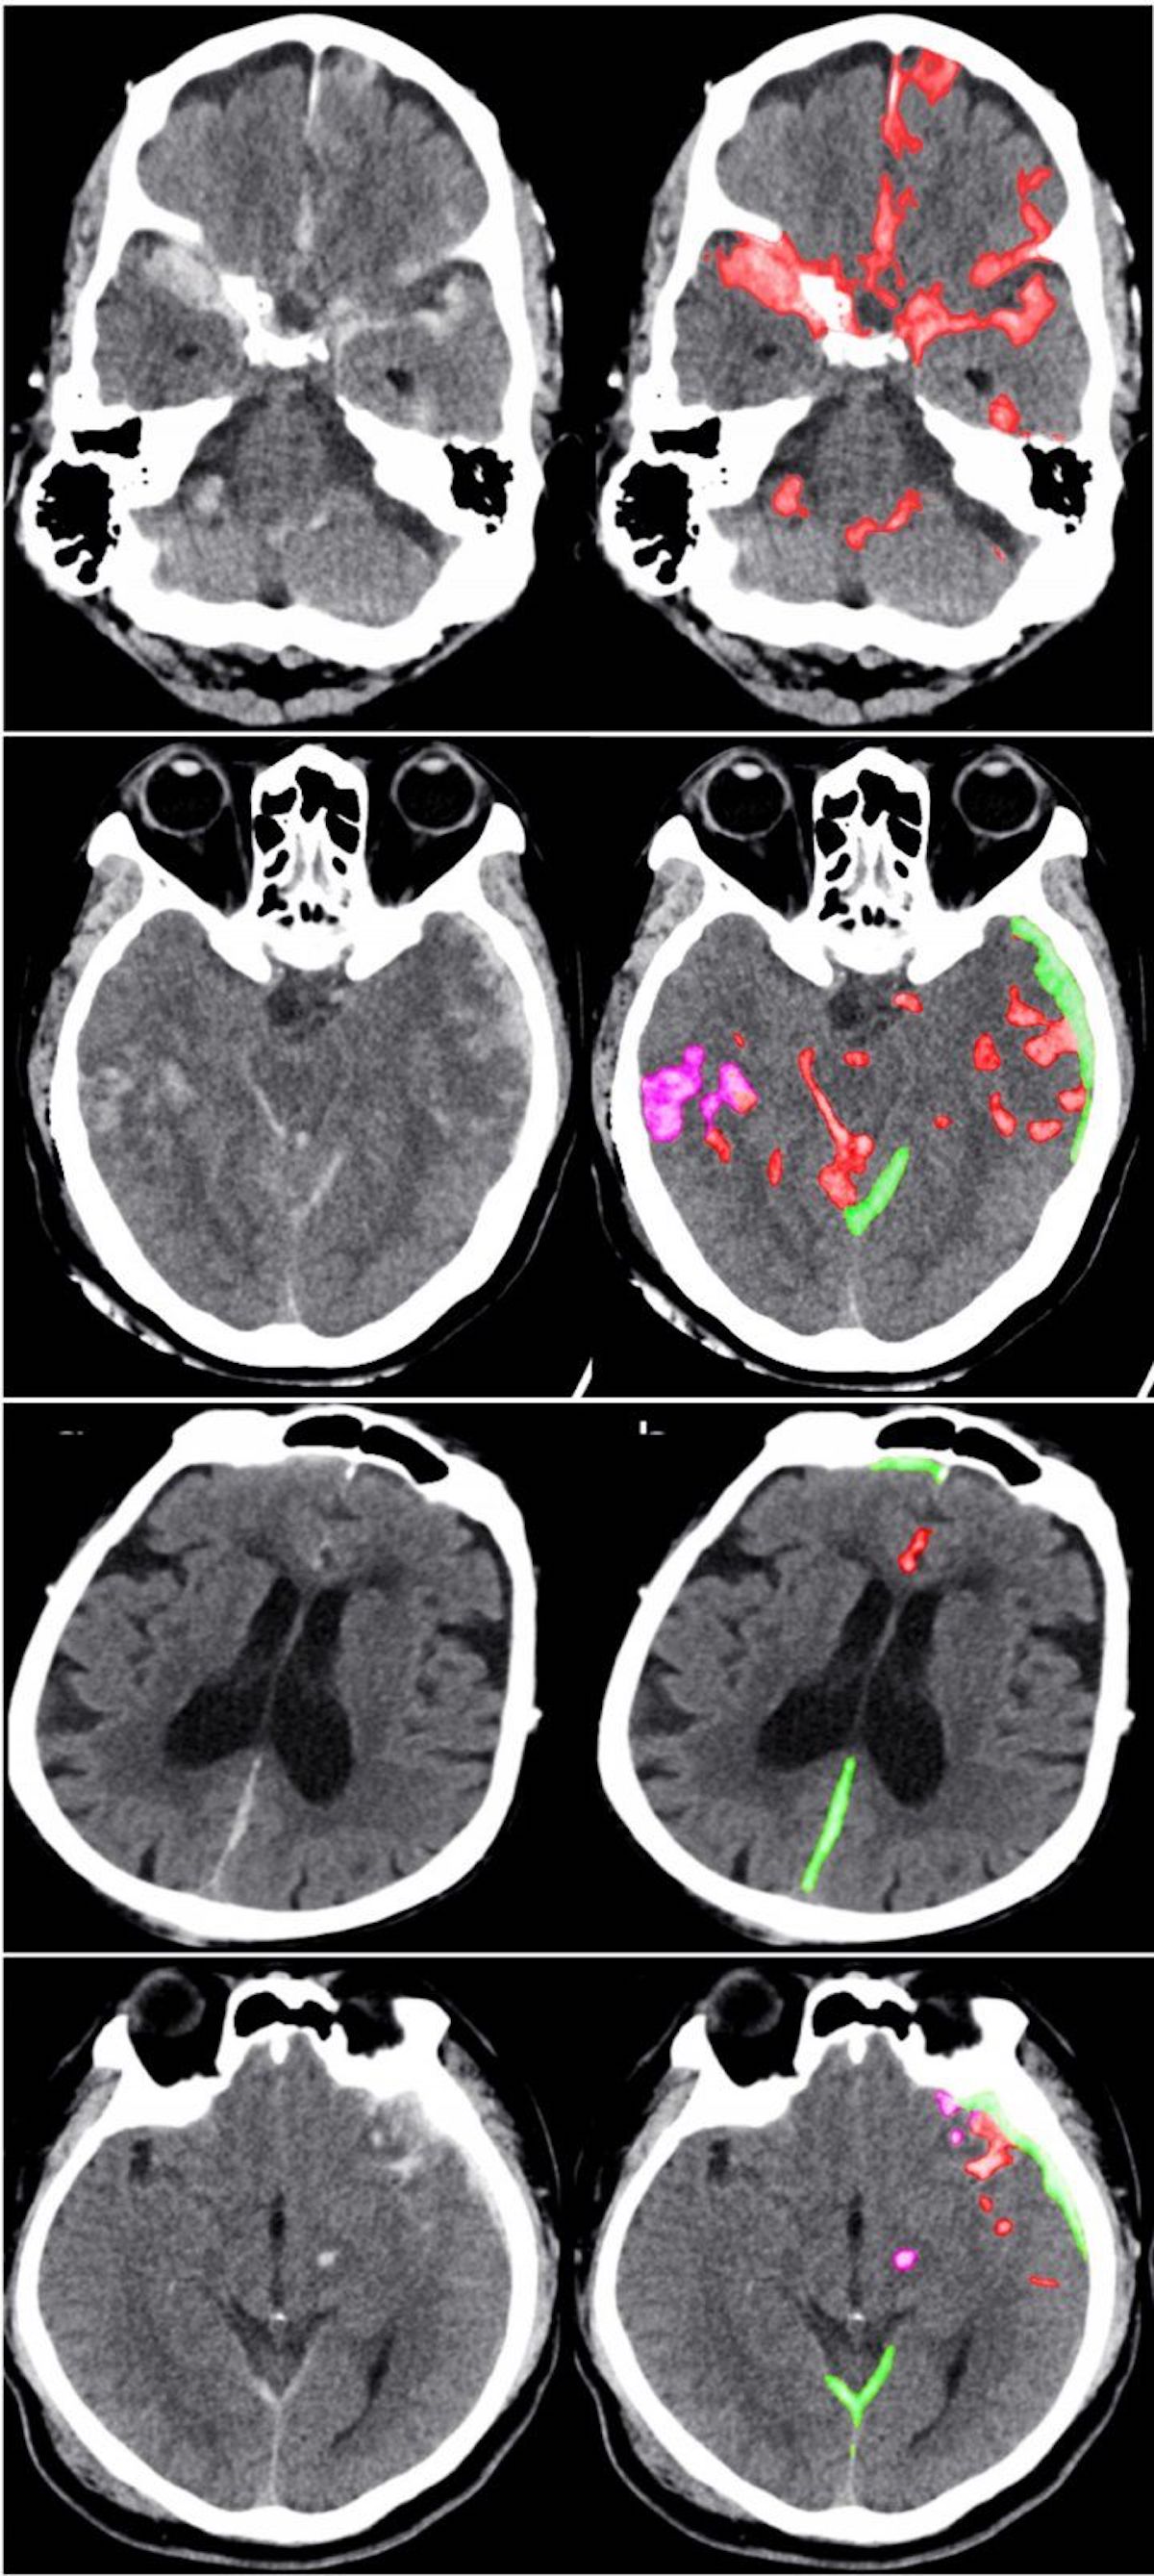

Il processo si basa sull’analisi di 4.396 scansioni CT. Questo è un numero relativamente piccolo di campioni, ma le anomalie sono state dettagliate “a livello di pixel”, secondo UCSF. In altre parole, l’intelligenza artificiale aveva molte meno probabilità di interpretare erroneamente il rumore e altri errori e individuare soltanto le vere emorragie. L’intelligenza artificiale viene addestrata a osservare una parte di un’immagine alla volta e non tutto l’insieme: questo tipo di osservazione ridurrebbe le possibilità di ipotesi errate.

Come altri sistemi di rilevamento basati sull’intelligenza artificiale, anche questo non sostituirà completamente i medici. Sarà invece di supporto: in pochi secondi può fornire un rapporto e può classificare automaticamente diversi tipi di emorragia, facendo risparmiare tempo prezioso ai medici in caso di emergenza e garantendo loro la possibilità di individuare emorragie difficilmente rintracciabili e che potrebbero essere fatali nelle peggiori circostanze.